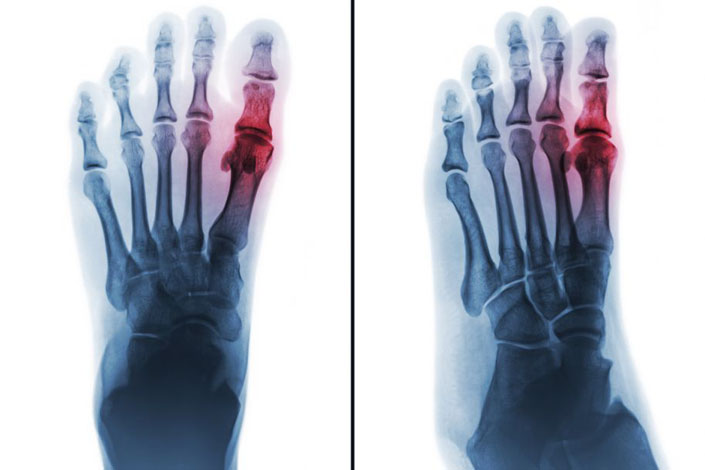

Leczenie bólu u pacjenta z ostrym napadem dny moczanowej

Pain management in a patient with an acute gout attack

Dna moczanowa jest chorobą metaboliczną wynikającą z odkładania się kryształów moczanu sodu, powodującą zarówno ostre napady zapalenia stawów i kaletek maziowych, jak również przewlekłe zapalenie stawów. Występuje u osób z hiperurykemią – podwyższonym stężeniem kwasu moczowego w surowicy, którego norma dla kobiet wynosi ok. 6 mg/dl, a dla mężczyzn ok. 6,8 mg/dl. Częstość występowania dny moczanowej stale się zwiększa; obecnie w Europie jest określana na poziomie 0,9–2,5% (1), a w USA – na 3,9% (2), wraz z narastającą epidemią otyłości i związanych z nią zaburzeń metabolicznych.